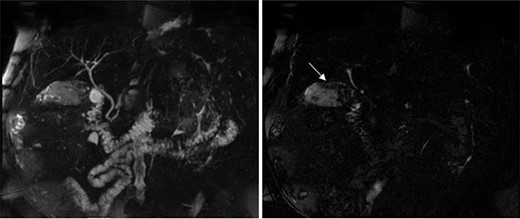

The preoperative work-up included a magnetic resonance cholangiopancreatography (MRCP), which showed a normal appearing biliary tree, but an abnormal appearing gallbladder with numerous gallstones and a space-occupying process involving the posterior wall (Fig. 2). The patient subsequently underwent an unremarkable laparoscopic cholecystectomy. Intraoperative findings revealed a distended, chronically inflamed gallbladder. No other suspicious findings were noted. Final pathology revealed a well-differentiated, 8 cm intracystic papillary neoplasm with high-grade dysplasia involving the majority of the gallbladder, with focally invasive adenocarcinoma invading the muscular layer of the gallbladder wall. These findings were consistent with a pT1bNx tumor.

MRCP showing a normal appearing biliary tree (left), but an abnormal appearing gallbladder with numerous gallstones and a space-occupying process (right marked by arrow) involving the posterior wall.